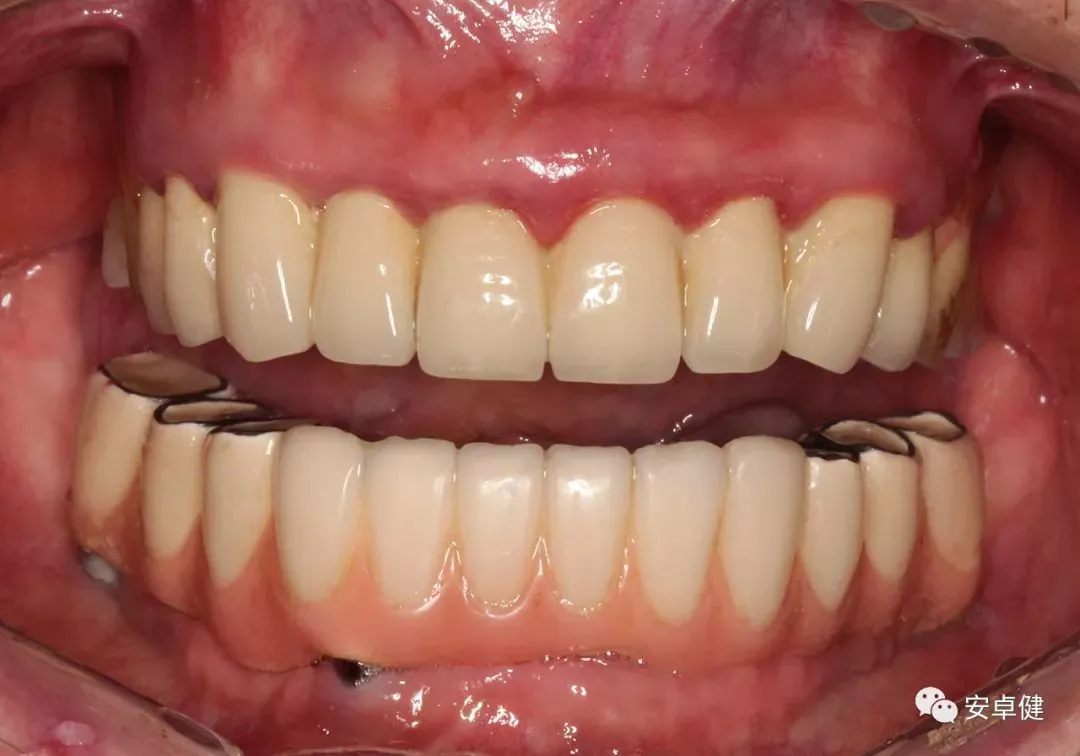

戴最终修复体正面咬合照

戴牙后4个月复诊正面咬合照

• 随访可见患者口腔卫生状况可,牙龈无红肿;

• 下颌修复体状态良好,无修复体机械并发症;

• 种植体基台稳定性良好,无松动;

• 种植体无松动,周围无红肿、溢脓及疼痛表现;

• 正中、前伸及侧方咬合检查可见咬合印记分布均匀,咬合关系良好;

• 患者反映日常使用良好,舒适性佳,满意度高。